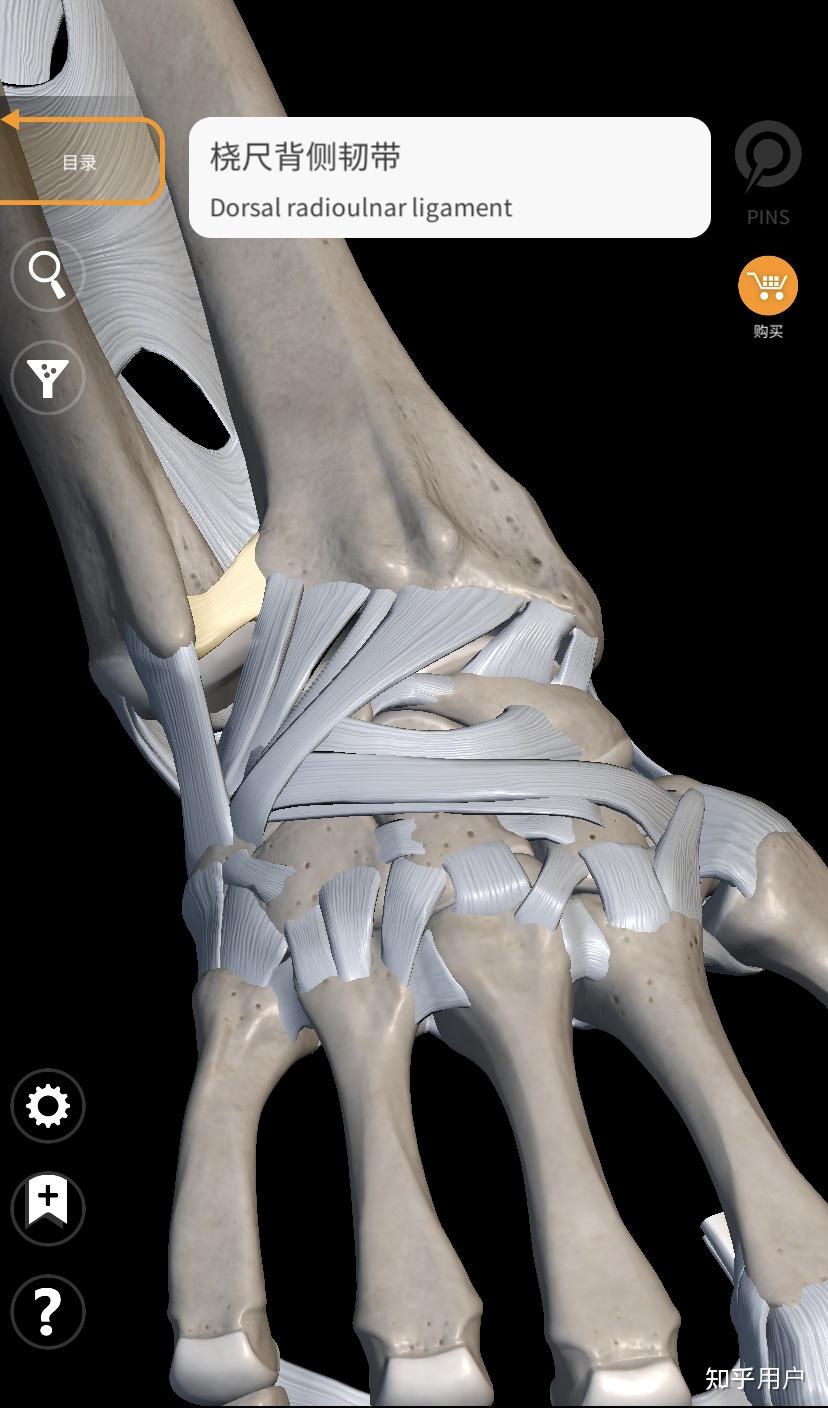

三角纤维软骨复合体(triangular fibrocartilage complex,tfcc)是指腕

三角纤维软骨复合体核心是一个软骨盘,周围有一圈韧带,像一个吊床一样